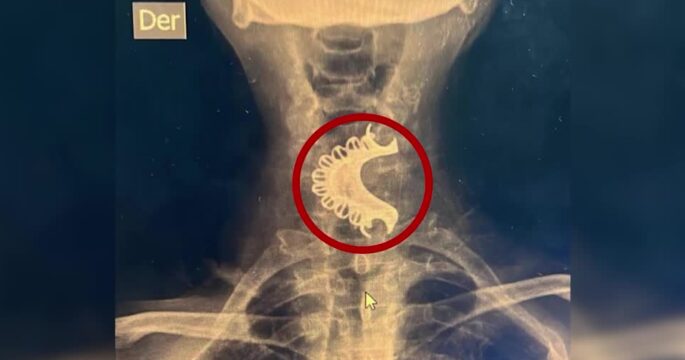

ลิมา 15 ม.ค.- คุณปู่คนหนึ่งในเปรูทำฟันปลอมร่วงลงไปติดอยู่ในคอโดยไม่รู้ตัว จนกระทั่งมีอาการเจ็บและหายใจลำบากจึงรู้ว่า สาเหตุเกิดจากฟันปลอมที่ติดอยู่ในลำคออยู่นานร่วมเดือน ศัลยแพทย์ศีรษะและคอผู้ทำการรักษาเปิดเผยเมื่อวันที่ 6 มกราคมตามเวลาท้องถิ่นว่า คุณปู่วัย 81 ปี ไปพบแพทย์ที่โรงพยาบาลในชุมชน เนื่องจากมีอาการเจ็บคอและหายใจลำบากโดยไม่ทราบสาเหตุมา 4 วัน คุณปู่มีประวัติรักษาโรคลมชักด้วยยากันชัก และคิดว่าฟันปลอมได้กระเด็นหลุดออกจากปากในระหว่างที่อาการกำเริบเมื่อวันที่ 13 ธันวาคมปีที่แล้ว แต่แท้จริงแล้วคุณปู่ได้เผลอกลืนฟันปลอมลงไปโดยไม่รู้ตัว แพทย์ที่โรงพยาบาลชุมชนนำตัวคุณปู่เข้าเครื่องเอ็กซเรย์ พบฟันปลอมทั้งแผงติดค้างอยู่ในบริเวณคอหอยส่วนล่าง จึงสอดท่อขนาดเล็กลงไปในลำคอเพื่อช่วยเรื่องทางเดินหายใจ แล้วส่งตัวไปรักษาต่อในโรงพยาบาลที่ทันสมัยกว่า โดยแพทย์ได้วิธีส่องกล้องและใช้เครื่องมือดึงเอาฟันปลอมออกมาจากคอได้อย่างปลอดภัย คุณปู่ออกจากโรงพยาบาลแล้วหลังจากที่พักฟื้นอยู่ในโรงพยาบาลไม่กี่วัน.-816(814).-สำนักข่าวไทย